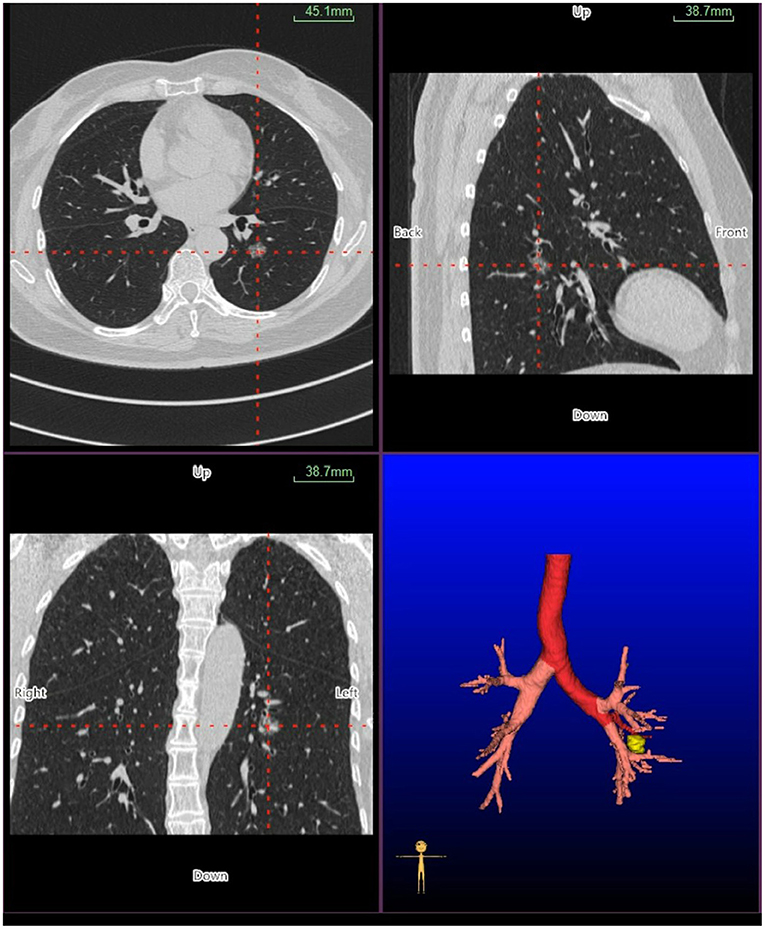

Virtual bronchoscopic navigation is a navigational technique that utilizes data of helical CT to construct three-dimensional virtual images of the bronchial route to guide the bronchoscope to the target lesion (Figure 1). Bf-NAVI® (Cybernet System Inc., Tokyo, Japan) was the first VBN system that was introduced in Japan in 2008, LungPoint® (Broncus Medical Inc., Mountain View, CA, USA) was launched in 2009 in the USA and is now widely used in the USA and European countries (10). DirectPath® (Cybernet System Inc.), which has replaced Bf-NAVI, is used in China by most centers. There are mainly 3 phases of virtual bronchoscopic navigation: planning, guidance, and biopsy. (i) Planning phase: In the planning phase, data from multi-detector chest CT of patients are imported to the computer via VBN software (Figure 2), which automatically creates the virtual bronchoscopic pathway to the target lesion (Figure 3). To obtain high-quality virtual bronchoscopic (VB) images, continuous volume CT data is required. Planning is a pre-bronchoscopy process that is usually done on the same day or days before the intended biopsy. (ii) Guidance phase: The virtual images acquired during the planning phase are used to advance the bronchoscope manually to the target lesion, and the position of the bronchoscope tip can be displayed on the CT images corresponding to the bronchial tree. (iii) Biopsy phase: The choice of procedure to biopsy lesion depends on patient selection and target disease. PPLs can be sampled with flexible bronchoscopy, ultrathin bronchoscopy, and radial endobronchial ultrasound probes (RP-EBUS).

Figure 2. Planning phase- multi-planar views of the target peripheral pulmonary lesion (axial, sagittal, coronal, and 3D map).